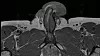

Bildet viser det vertikale bruddet i 40-åringens penis.

Ifølge rapporten fra legene på saken er dette det første registrerte tilfellet av et vertikalt penisbrudd.